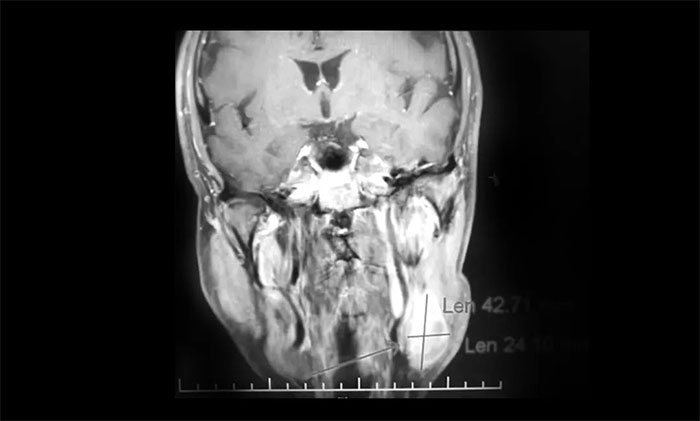

经MDT多学科会诊评估,制定以放疗为主的同步放化疗方案。治疗后复查MRI,患者左侧鼻咽部实性占位较前治疗明显减小;原左侧下颌腺区、咽旁肿大淋巴结已基本吸收好转,左颈部肿大淋巴结较前明显缩小。

▲ 放疗后复查MRI,肿瘤占位较前明显减小